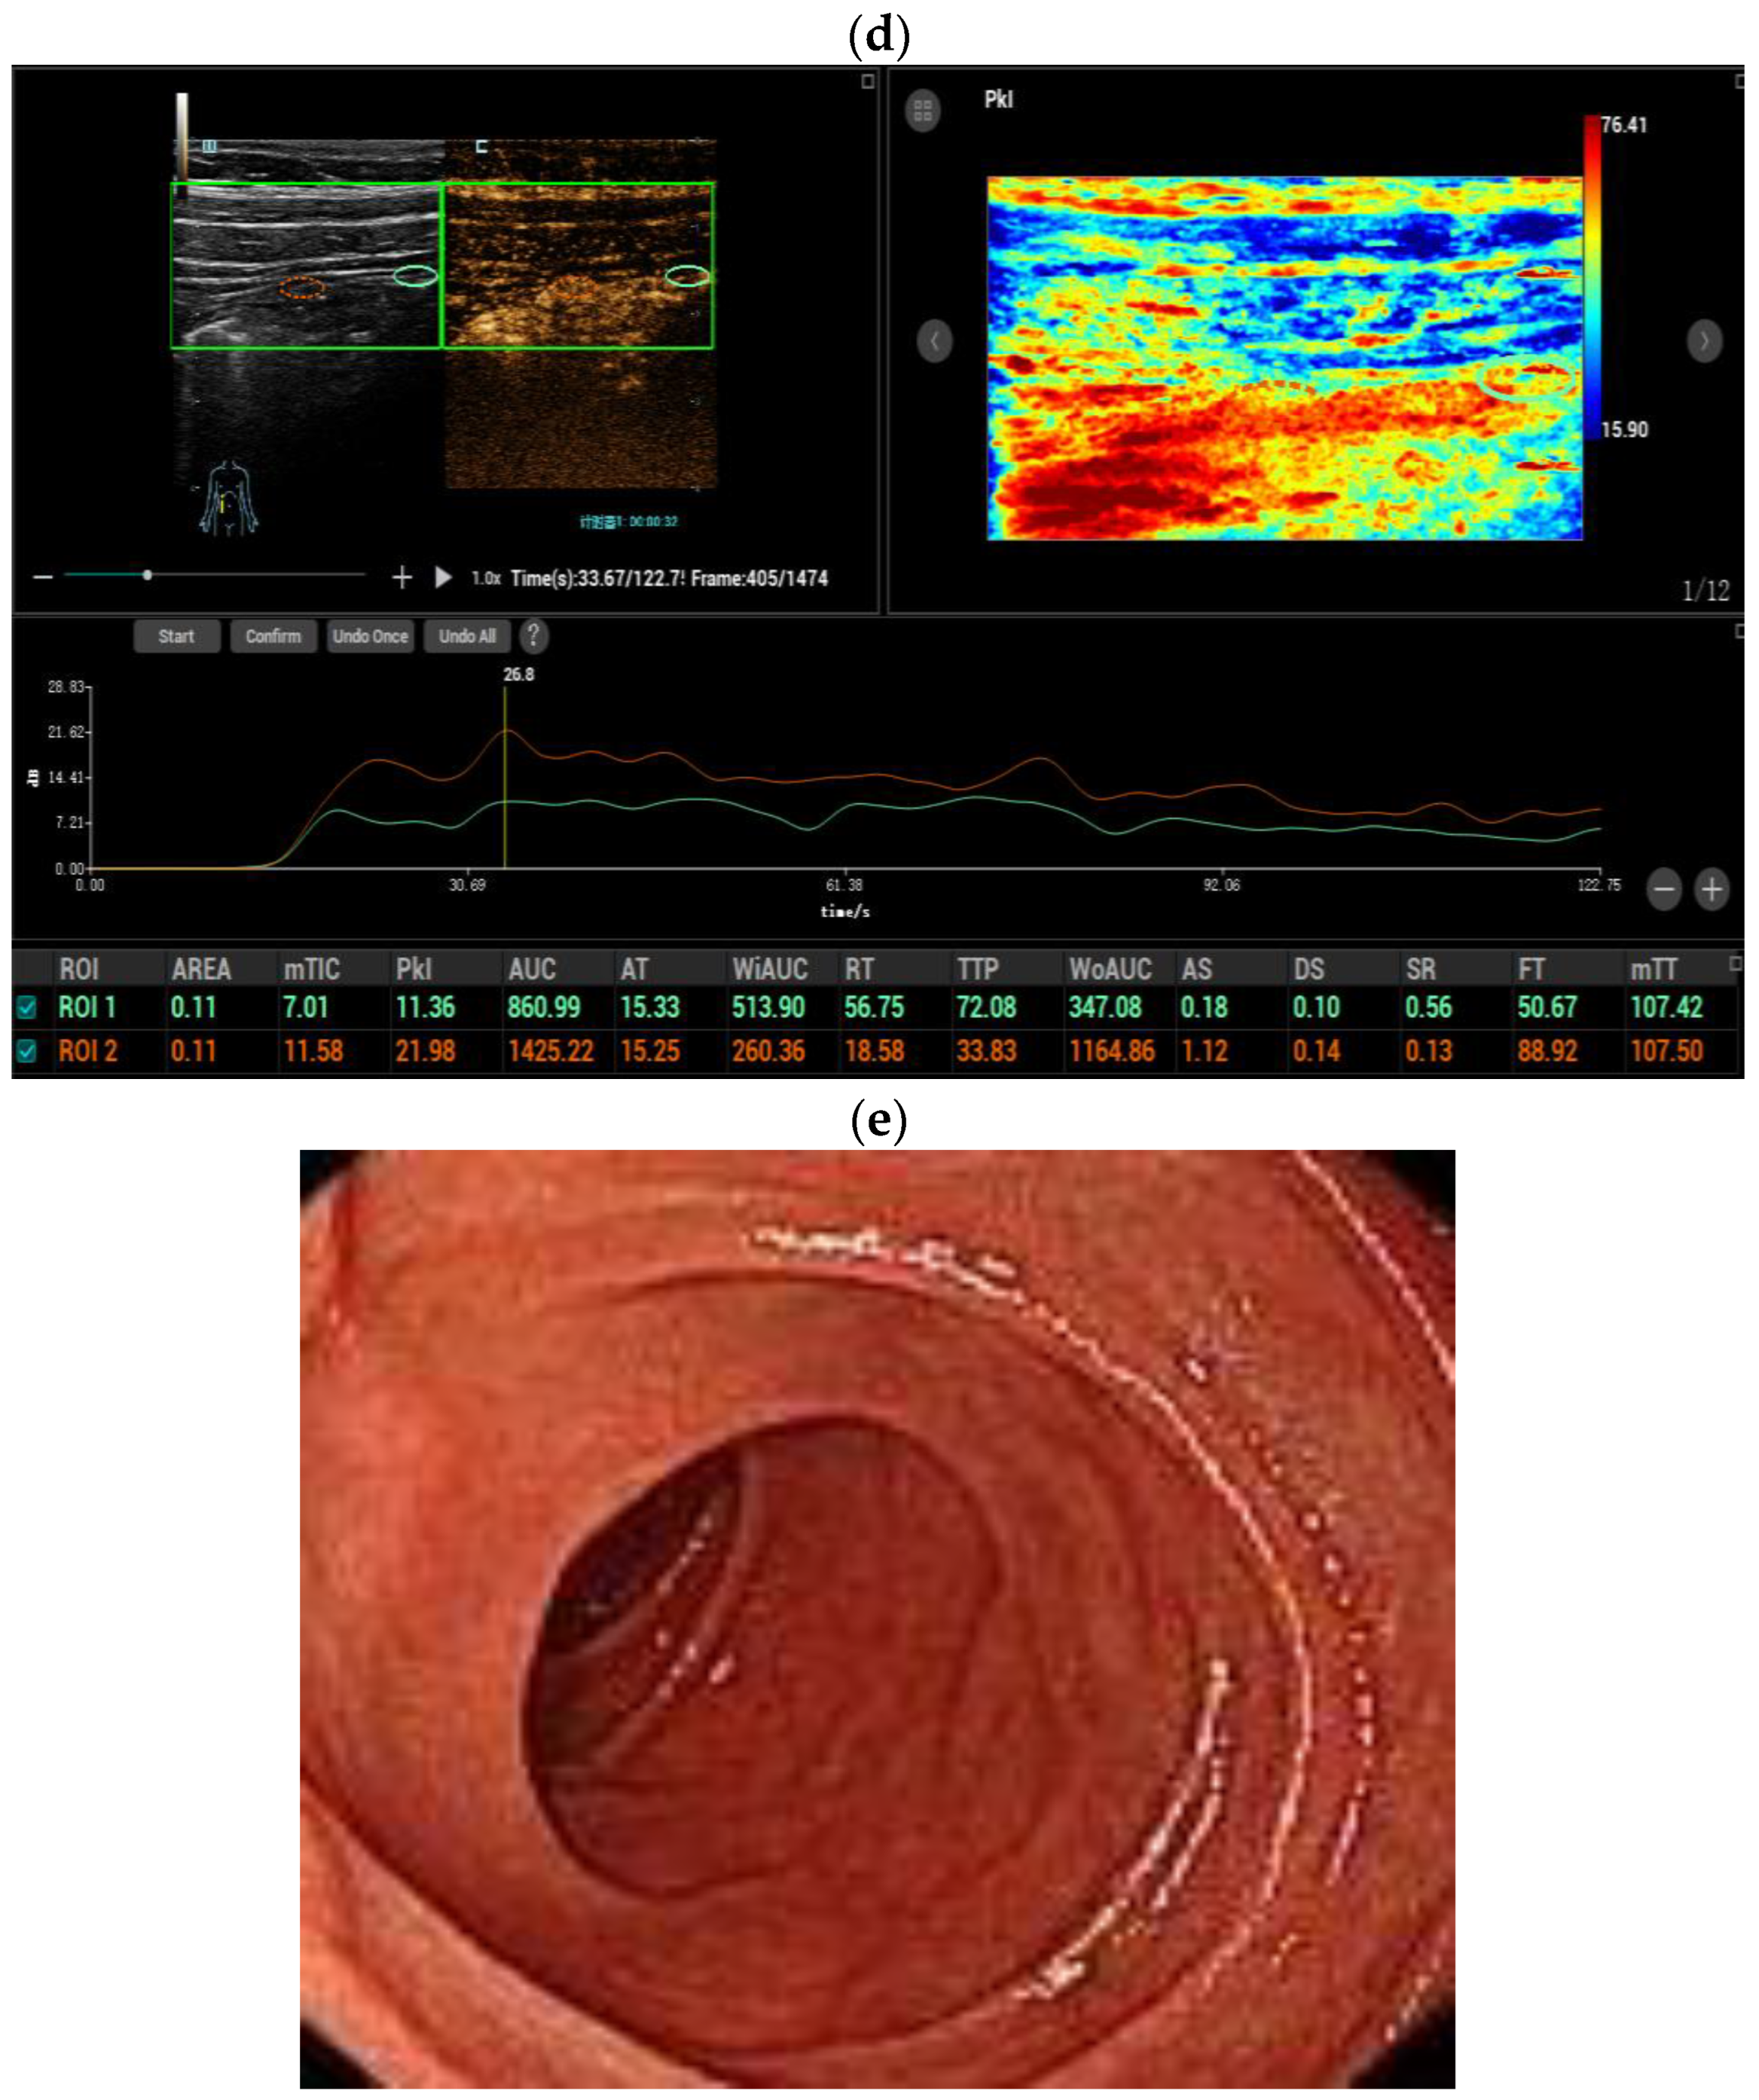

3.3. Dynamic Contrast-Enhanced Ultrasound (DCE-US) Quantitative Analysis

- Huang, Y.; Wang, Y.; Liu, L.; Zhu, L.; Qiu, Y.; Zuo, D.; Lu, X.; Dong, Y.; Jung, E.M.; Wang, W. VueBox(R) perfusion analysis of dynamic contrast enhanced ultrasound provides added value in the diagnosis of small thyroid nodules. Clin. Hemorheol. Microcirc. 2023, 83, 409–420. [Google Scholar] [CrossRef] [PubMed]

- Yang, D.H.; Cheng, J.; Tian, X.F.; Zhang, Q.; Yu, L.Y.; Qiu, Y.J.; Lu, X.Y.; Lou, W.H.; Dong, Y.; Wang, W.P. Prediction of Pathological Grades of Pancreatic Neuroendocrine Tumors Based on Dynamic Contrast-Enhanced Ultrasound Quantitative Analysis. Diagnostics 2023, 13, 238. [Google Scholar] [CrossRef] [PubMed]

- Dong, Y.; Chen, S.; Moller, K.; Qiu, Y.-J.; Lu, X.-Y.; Zhang, Q.; Dietrich, C.F.; Wang, W.-P. Applications of Dynamic Contrast-Enhanced Ultrasound in Differential Diagnosis of Hepatocellular Carcinoma and Intrahepatic Cholangiocarcinoma in Non-cirrhotic Liver. Ultrasound Med. Biol. 2023, 49, 1780–1788. [Google Scholar] [CrossRef]

- Lu, X.Y.; Guo, X.; Zhang, Q.; Qiu, Y.-J.; Zuo, D.; Chen, S.; Tian, X.-F.; Zhou, Y.-H.; Dong, Y.; Wang, W.-P. Early Assessment of Chemoradiotherapy Response for Locally Advanced Pancreatic Ductal Adenocarcinoma by Dynamic Contrast-Enhanced Ultrasound. Diagnostics 2022, 12, 2662. [Google Scholar] [CrossRef]

- Dietrich, C.F.; Correas, J.M.; Cui, X.W.; Dong, Y.; Havre, R.F.; Jenssen, C.; Jung, E.M.; Krix, M.; Lim, A.; Lassau, N.; et al. EFSUMB Technical Review—Update 2023: Dynamic Contrast-Enhanced Ultrasound (DCE-CEUS) for the Quantification of Tumor Perfusion. Ultraschall Med. 2024, 45, 36–46. [Google Scholar] [CrossRef]

- Girlich, C.; Jung, E.M.; Iesalnieks, I.; Schreyer, A.G.; Zorger, N.; Strauch, U.; Schacherer, D. Quantitative assessment of bowel wall vascularisation in Crohn’s disease with contrast-enhanced ultrasound and perfusion analysis. Clin. Hemorheol. Microcirc. 2009, 43, 141–148. [Google Scholar] [CrossRef] [PubMed]